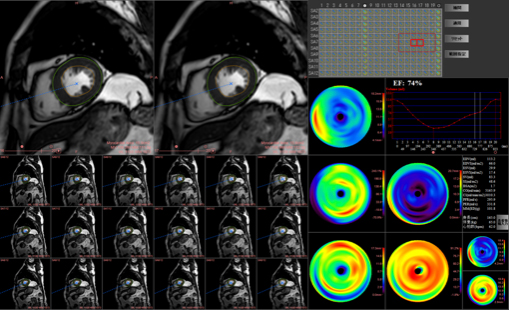

左心室機能解析:心臓の機能解析が可能です。

T1 mapping:左心室の性状評価が可能です。